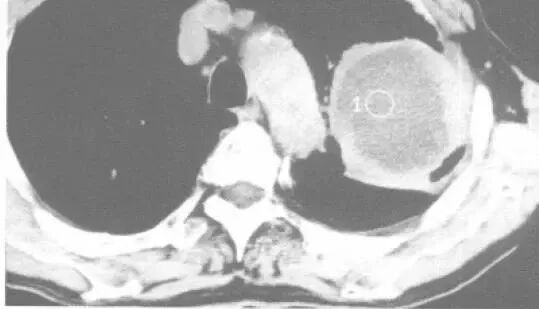

这是什么?

答曰:几乎是鳞癌。

为什么?

因为:鳞癌最容易烂掉!鳞癌天生的烂!乱七八糟的空洞,肿瘤内液化坏死,等等,大部分是鳞癌

肿块+液化坏死 ≈ 鳞癌。